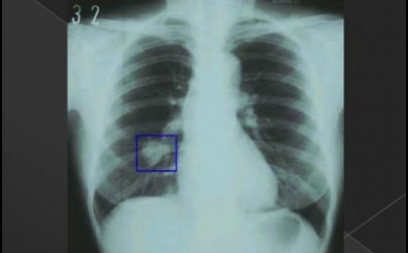

이번 기사에서는 폐암 초기 증상에 대해 자세히 정리해 알려 드리겠습니다 . 폐암은 국내암 사망률 1 위로, 과거에는 흡연이 폐암의 주된 원인 이었지만 , 현재는 비흡연 폐암 환자도 대폭 증가했습니다 . 폐암은 의학 기술로 발달하여 생존율이 높아지고 있습니다 . 폐암의 초기 증상은 무엇인가를 알아보겠습니다.

폐암의 초기 증상